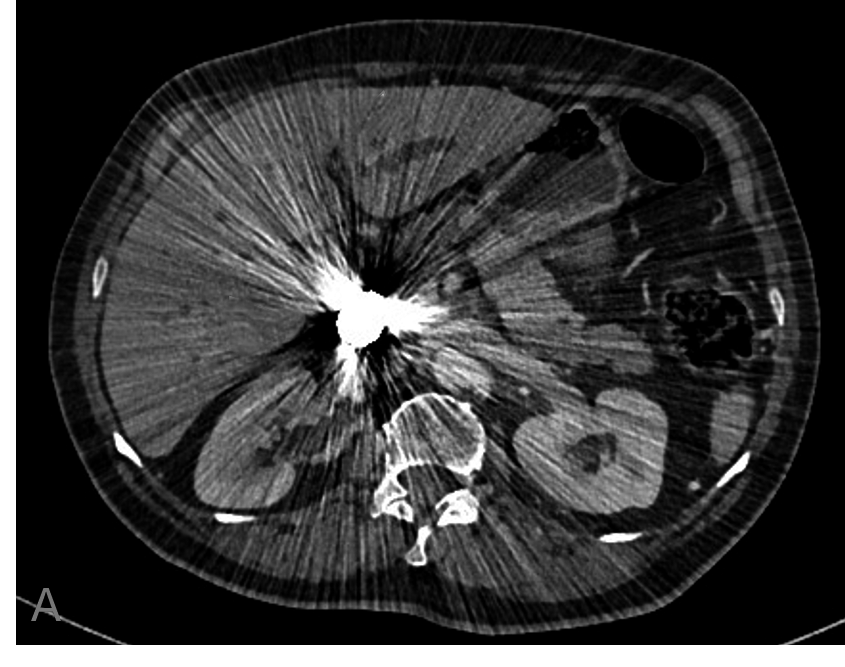

Se le realizaron estudios de imagen de control. En TC de control al año (Fig.6) se visualizan los coils, que no se han modificado, y que condicionan artefacto metálico que dificulta la valoración, el pseudoaneurisma permanece embolizado y la arteria hepática derecha permeable, se observa además progresión de su enfermedad basal, por crecimiento del colangiocarcinoma y dilatación de la vía biliar intrahepática.